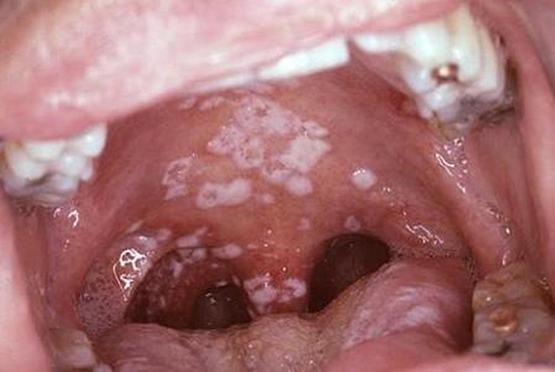

Theo BS. Phương, bệnh nấm thực quản rất dễ nhìn thấy khi khám vì các mảng trắng bám vào niêm mạc miệng, lưỡi và họng một cách riêng lẻ hoặc kết nối với nhau. Tuy nhiên khi nhìn thấy rõ các mảng bám trong niêm mạc miệng là bệnh nấm thực quản đã ở giai đoạn nặng. Còn nếu các mảng bám nằm ở cuối lưỡi hoặc đầu họng thì mắt thường khó nhìn thấy vì đang nằm trong giai đoạn viêm thực quản nên triệu chứng lâm sàng không rõ ràng.

Lúc đó chỉ nhờ soi chiếu các BS mới phát hiện ra được căn bệnh này. Hệ thống đường tiêu hóa của cơ thể người trải dài từ miệng đến hậu môn với nhiều phần khác nhau. Do sống ký sinh nên nấm Candida có thể khu trú ở một số địa điểm trọng yếu như thực quản, dạ dày hoặc đại tràng. ở bất cứ vị trí nào chúng cũng có thể tấn công toàn bộ đường tiêu hóa và gây nên nhiều triệu chứng khác nhau.